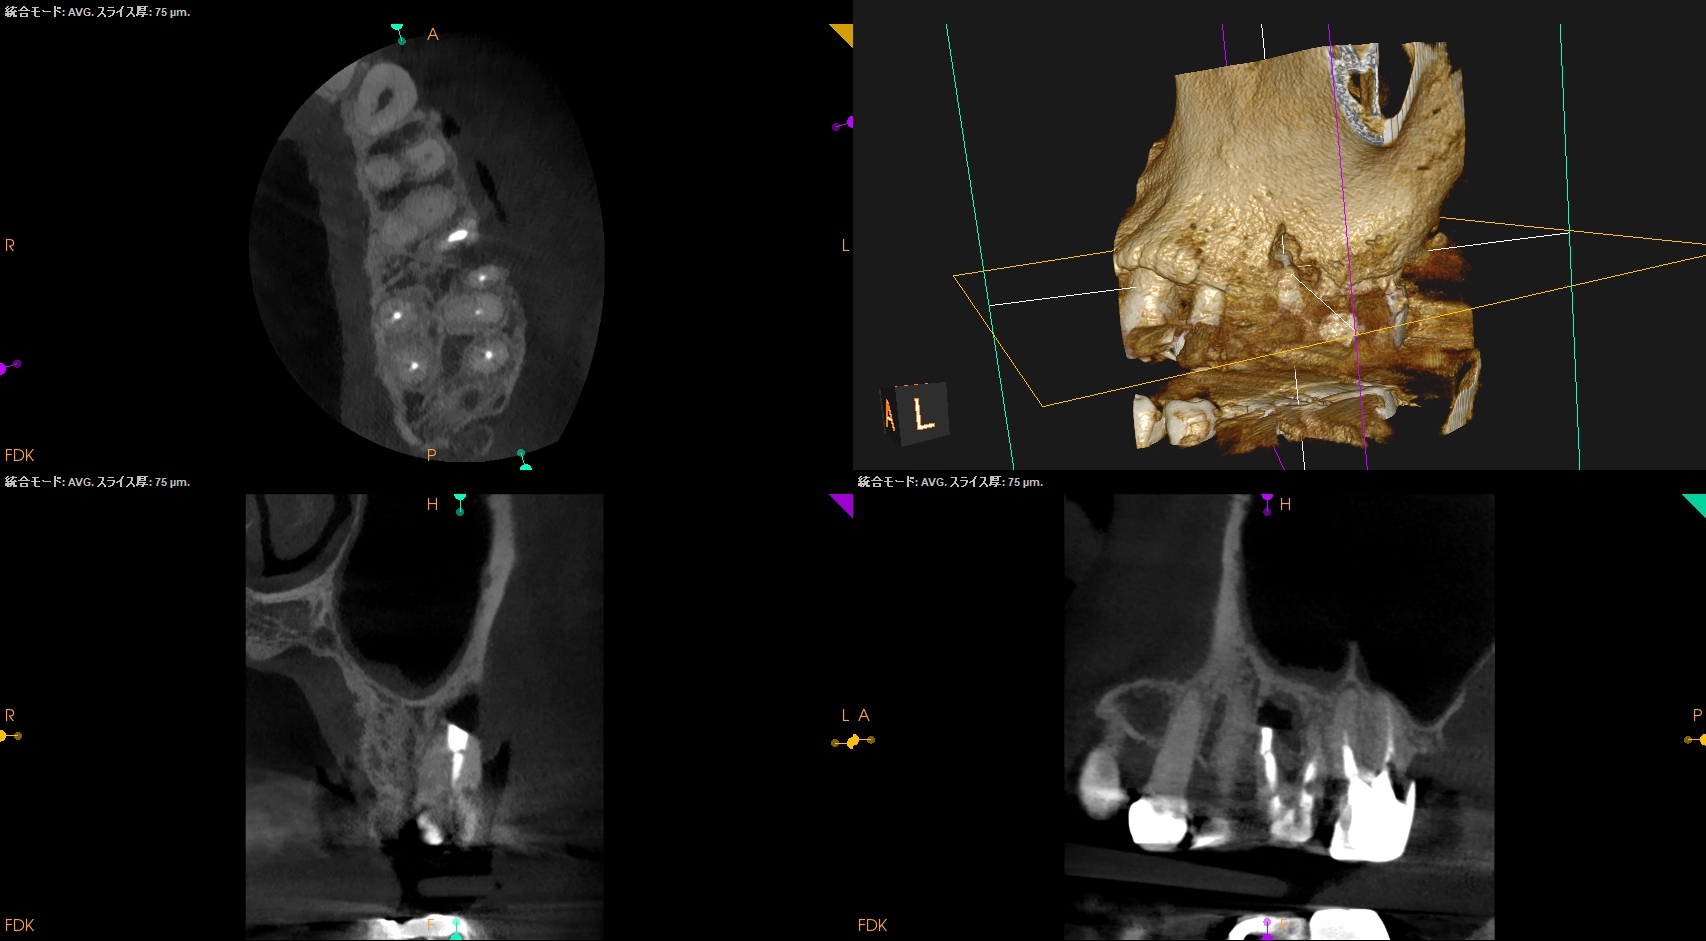

CBCTから当該Apex相当部位を確認しOsteotomyしてRoot resectionし、メチレンブルーで染色した。

その時の絵がCBCTでMBを3mmで切断した

この絵と相似形なので問題はないと考えた。

この後、RetroprepしRetrofillした。

PA, CBCTを撮影した。

問題はないだろう。